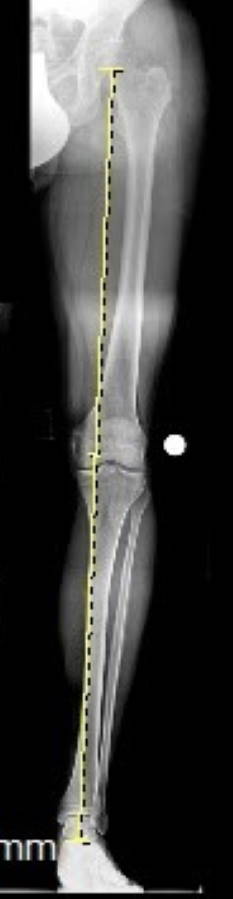

Im ersten Schritt erfasst der Orthopäde die vorliegende Fehlstellung der Beinachse in einer ausführlichen klinischen Untersuchung. Dabei schätzt er die Beinachse im Stehen inspektorisch ein. Röntgenaufnahmen des gesamten Beins von Hüfte bis Fuß lassen das Ausmaß der Achsabweichung exakt bestimmen. Anhand der Bilder kann der Orthopäde die notwendigen Korrekturen planen.